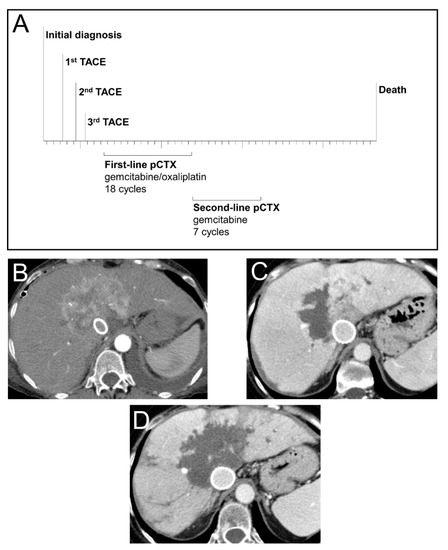

3.5. Case Study